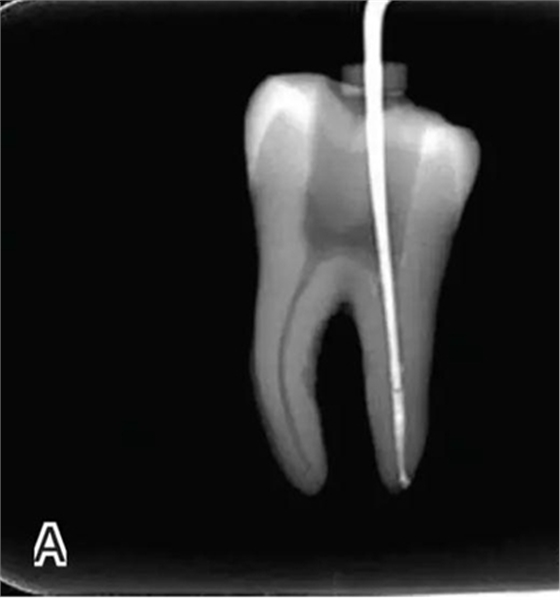

3、試尖

選擇非標(biāo)準(zhǔn)牙膠尖(如0.04、0.06 錐度牙膠尖)作為主尖,型號一般與根管預(yù)備最大號的器械型號一致,能到達(dá)距根尖0.5~1 mm 處,主尖尖段與根管壁緊密接觸。拍試尖X 線片進(jìn)行確認(rèn)(圖3)。

圖3 試尖,A.試主尖 B.拍試尖X片